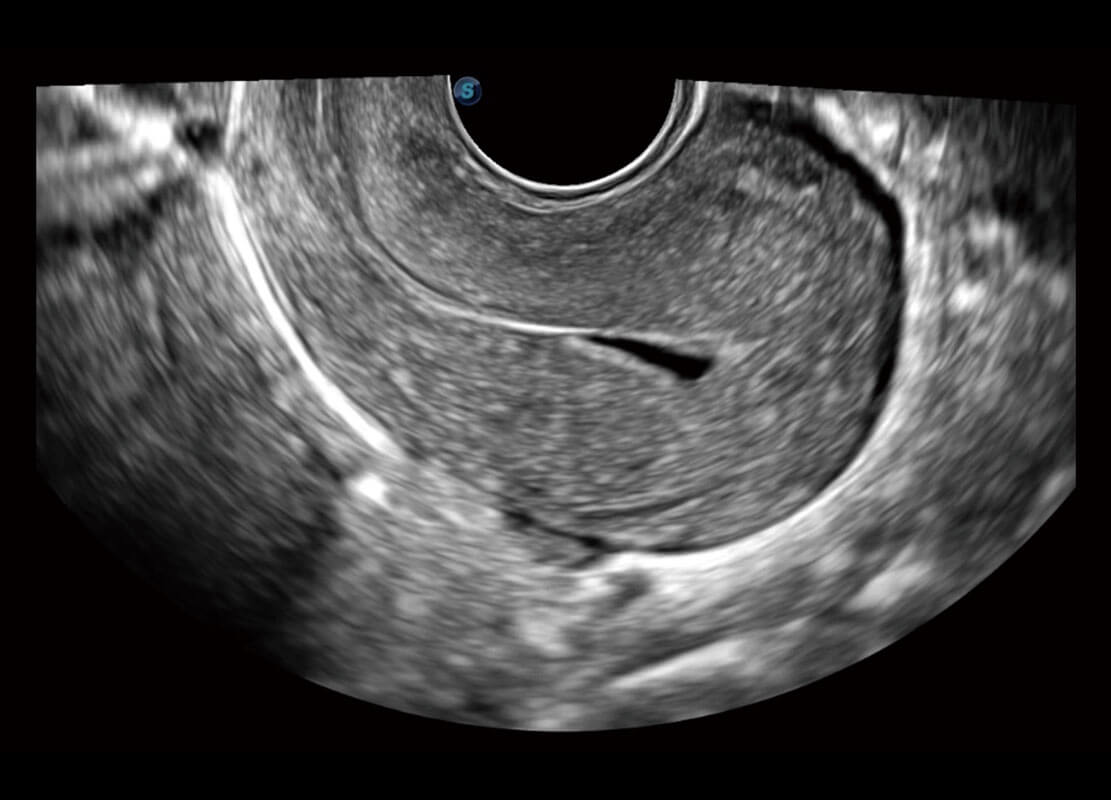

盆底超声

P60为盆底超声检查提供应用方案,多种腔内及腹部容积探头提供从二维、三维到四维的优异图像品质,实时快速三维容积数据获取,专业的测量工具包等人性化设计,为超声医生诊断提供有力保障。

Lev.Hiat A-r: 16.33 cm2

Lev.Hiat H-r: 53.70 mm

Lev.Hiat W-r: 43.96 mm

Lt-LUG-r: 24.16 mm

Rt-LUG-r: 19.94 mm

S-Pelvic

能够简化盆底检查的操作流程,可在二维模式及三维成像模式下实现一键自动提取出标准切面、自动识别当前切面、自动测量,提升盆底检查的高效性,同时也能让青年医生快捷的获得准确的检查结果。